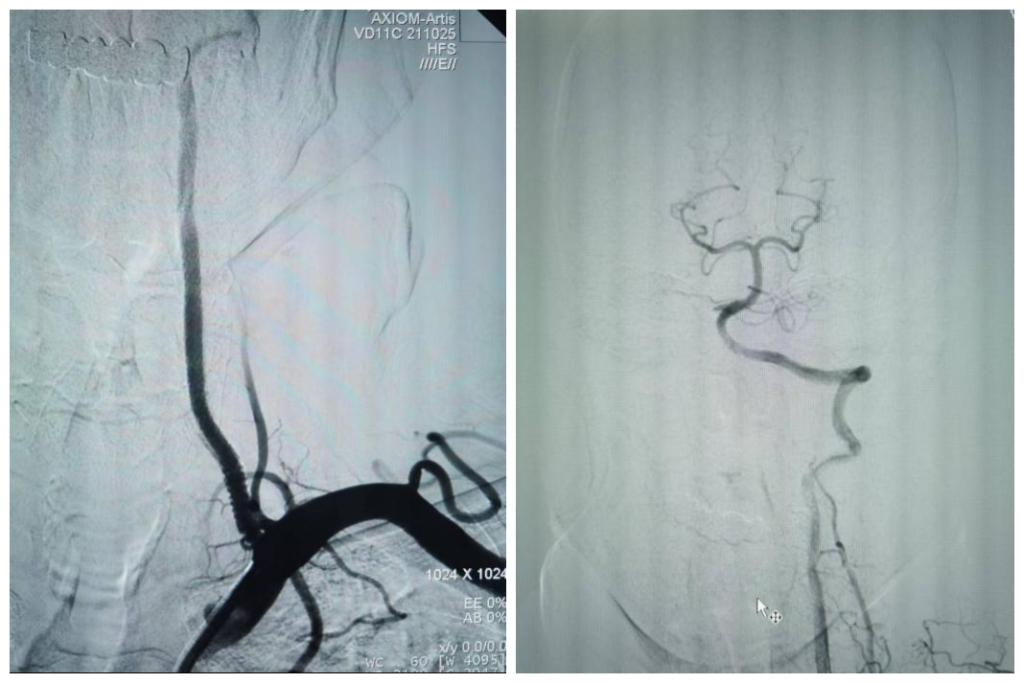

最终,在患者入院第4天,张桂莲教授带领的介入团队选择局麻条件下为患者成功实施了神经介入领域的高难度手术—左侧无残端椎动脉长节段慢性闭塞再通术。因术前清晰的影像显影及准确的体外定位标记,左侧优势椎动脉顺利开通,手术耗时仅仅约90分钟。术中及术后患者配合良好,无任何不适,术后在介入准备室,张桂莲教授向患者女儿详细告知手术过程及患者目前状况,患者女儿喜极而泣,多次向介入团队表示感谢。

出院前复查头颈一体化超声提示左侧椎动脉支架位置良好,血流通畅,颅内血流速度及频谱未见明显异常。充分向患者及家属告知出院注意事项及复查时间后,目前该患者已顺利出院。